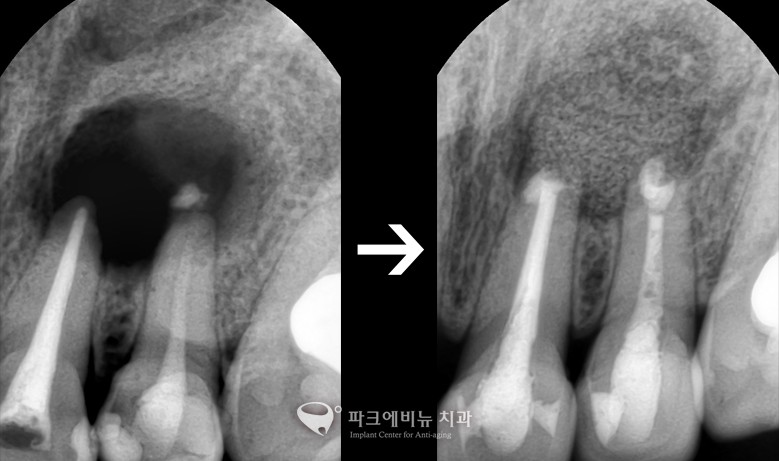

* 충치신경치료를 여러 번 해도 낫지 않는 뿌리 끝 염증! 어떻게 할까?

치근단절제술

치수에 염증이 있거나, 세균에 감염이 되어 치아 뿌리 끝에 염증이 생긴 경우 근관 치료를 시행 한 후 치아 뿌리 끝 주변의 조직들은 치료가 되지 않는 경우가 많다. 이럴 경우, 치아 뿌리 끝에 있는 치조골 주변의 염증 조직을 치아 뿌리 끝 부분을 잘라내게 되는 수술이다. 이 수술을 받는다면, 치아를 뽑지 않고 보존을 시킬 수 있다는 장점이 있다. 근관 치료는 치수에 염증이 있거나 세균에 감염이 되었을 때 손상된 치수를 제거하는 방법이다. 이 수술 후 제거된 치아 뿌리 끝 중심부에 구멍을 낸 후 충전물을 채워 완전히 막는다. 염증 부위가 넓을 경우에는 뼈가 잘 형성이 되도록 약을 넣어주기도 하고, 수술한 부위를 봉합하고 수개월이 지나게 된다면 치아 뿌리 주변에 뼈가 차게 된다. 때로는 염증 부위가 커서 골 소실 양이 많은 경우 뼈 이식을 통해 보강을 할 수도 있다.